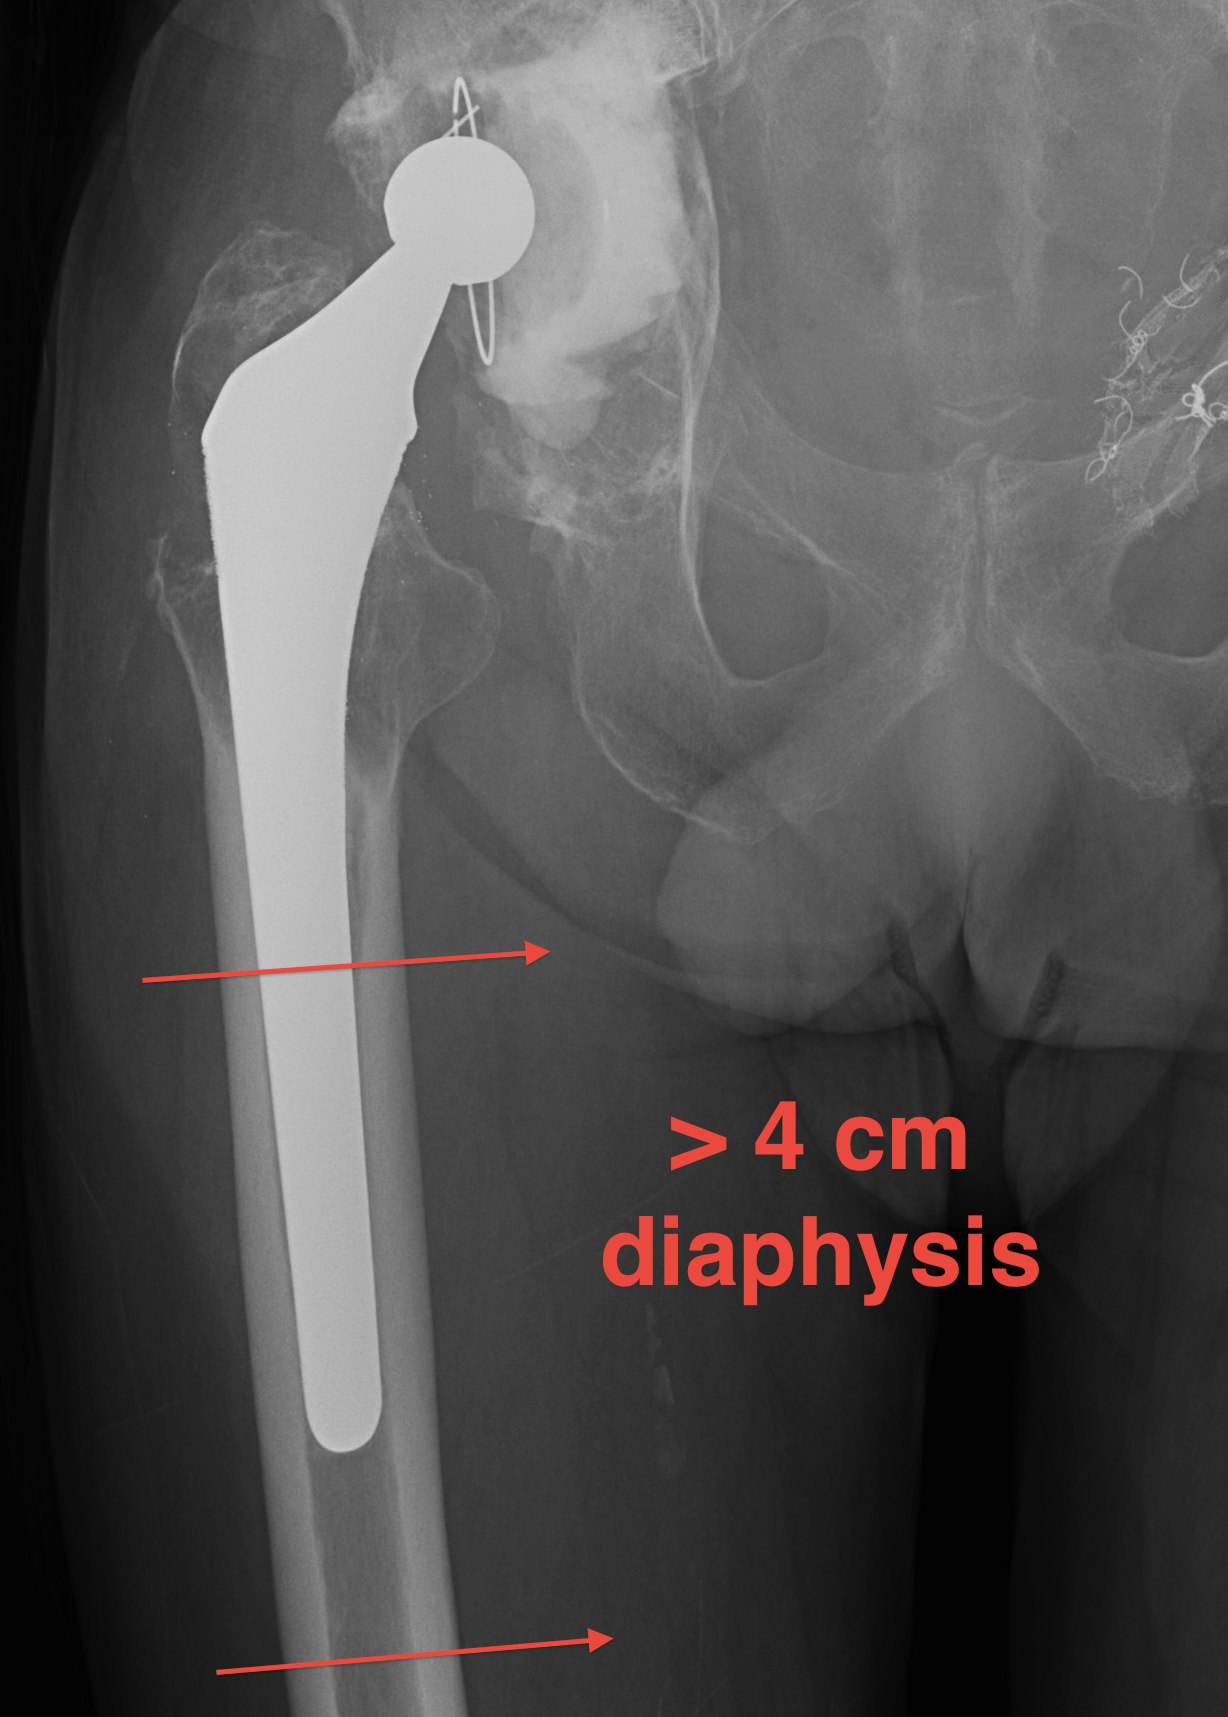

IIIA Metaphysis severely damaged / > 4cm diaphyseal bone for distal fixation

- grossly loose femoral component

- first generation cementing techniques